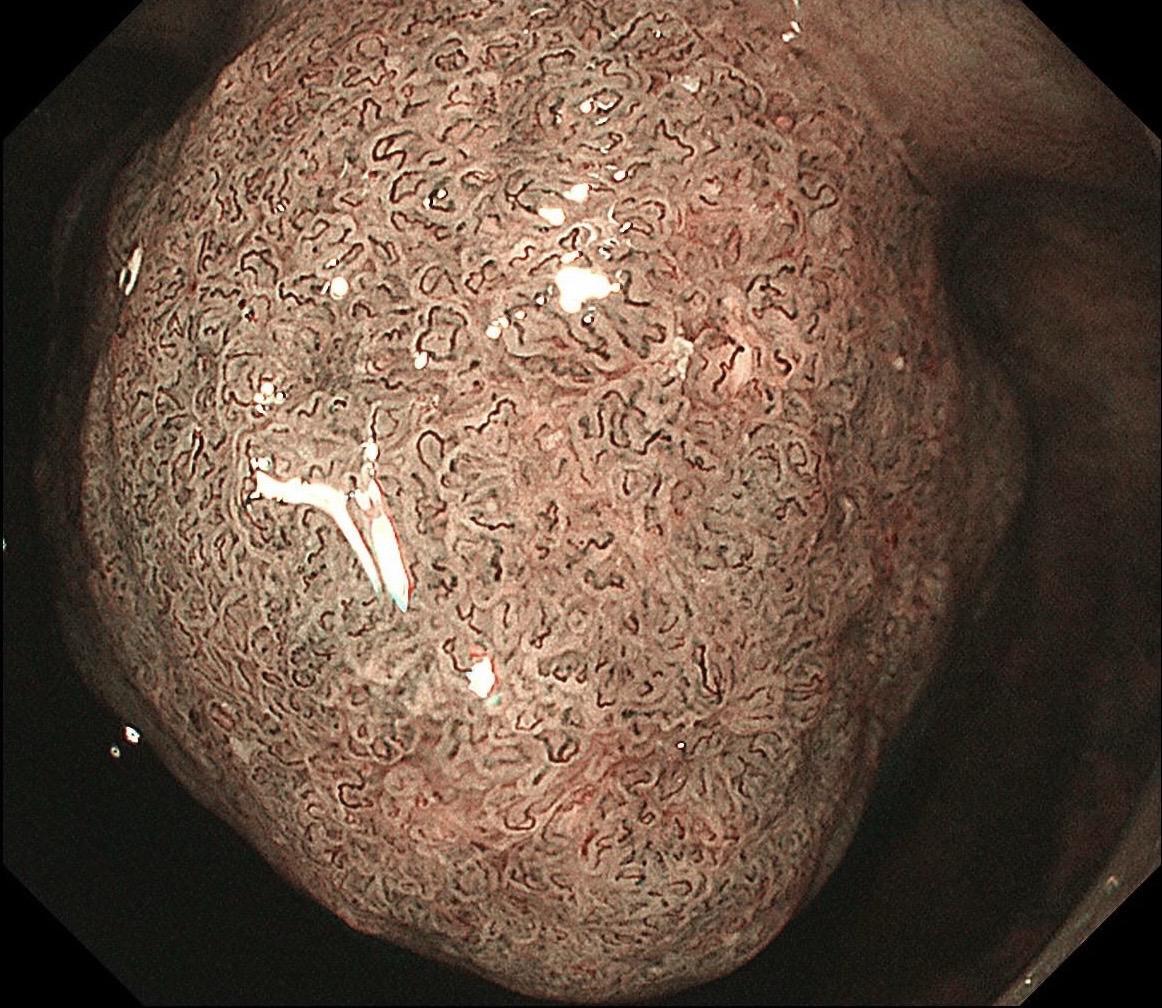

低位早期直肠Ca.男,37岁,大便带血1月,距齿状线2cm,ESD切除,还好来得及时~